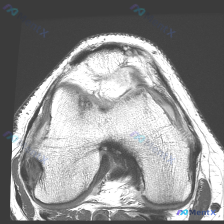

今天碰到一个很典型的「临床-影像矛盾」病例,整理出来和大家一起讨论一下。 病例核心信息 问题:临床高度怀疑膝关节软骨异常,仅提供1张膝关节MRI-T1序列轴位影像(髌股关节层面),要求读片分析。 影像读片结果: 1. 骨性结构:股骨远端、髌骨骨皮质连续,软骨下骨光滑,骨髓脂肪信号均匀,未见异常信号灶...

今天遇到一个有意思的读片问题:只给了一张膝关节轴位MRI,问这里有没有软骨异常,整理一下分析思路分享给大家。 基本病例/影像信息 提供的是膝关节单张轴位MRI扫描图像,可识别的解剖结构包括:前方的髌骨、中部的股骨内外侧髁与髁间窝、髌股关节间隙,以及周围部分软组织。 客观影像所见 1. 软骨结构:髌骨...

看到一份针对单张膝关节MRI的软骨异常评估咨询,整理了完整的分析思路分享给大家。 病例/影像基础信息 问题核心:用户提供单张膝关节轴位T1加权MRI图像,询问图像中是否存在软骨异常。 影像所见(基于提供图像): 1. 扫描层面为膝关节轴位,涵盖股骨远端滑车区与髌骨 2. 股骨髁、髌骨骨髓信号正常(T...

刚遇到一份有意思的膝关节影像病例,整理出来和大家分享一下思路。 病例基本信息 这是一份膝关节MRI T1序列轴位单张图像,核心疑问是评估是否存在「软骨异常」。 影像读片结果 1. 扫描层面是膝关节上部,主要显示髌股关节(髌骨+股骨滑车)和股骨髁 2. 髌骨软骨下骨、股骨髁骨皮质轮廓清晰,骨松质信号均...

看到这个病例挺有代表性,整理了完整资料和分析思路分享给大家。 病例基本资料 本次分析基于1张膝关节T2加权轴位MRI(髌股关节层面),临床提示为「软骨异常」,具体临床症状未提供。 影像学所见 1. 髌股关节结构:髌骨位于滑车槽中央,对位关系尚可,无明确脱位/半脱位;关节间隙无狭窄,仅可见少量生理性高...

病例读片:膝关节软骨异常的影像陷阱 先给大家看一下这份病例的基本影像资料:这是一张膝关节MRI-T1加权序列的轴位图像,扫描层面位于股骨远端髁间窝与髌股关节层面。 影像基本信息整理 1. 骨骼结构:股骨远端骨皮质、骨髓信号正常,髌骨形态完整,骨皮质连续,骨髓信号无异常; 2. 关节软骨:髌骨后方关节...